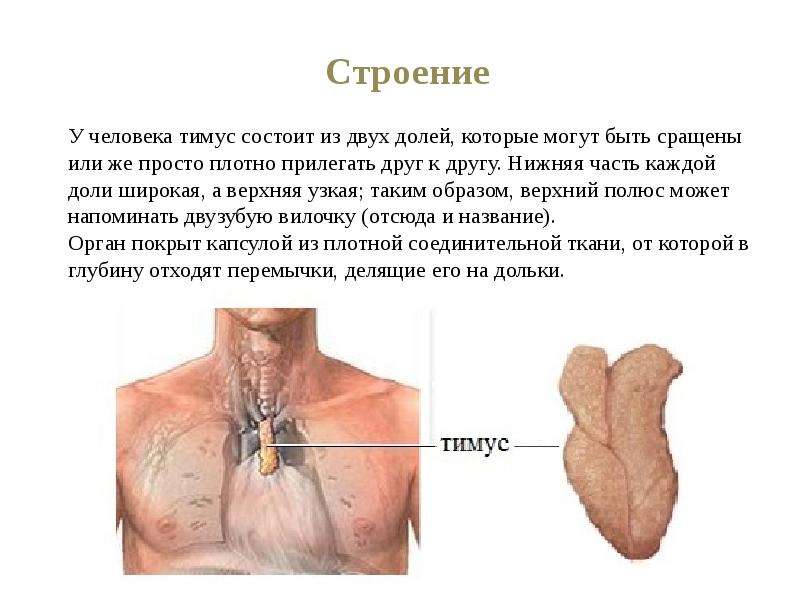

Фотографии вилочковой железы тимуса: структура и функции